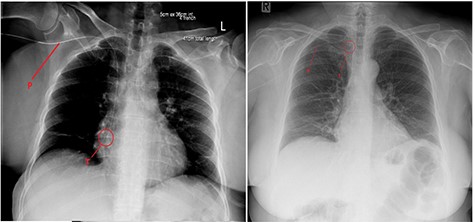

The PICC line was inserted into the right arm under ultrasound guidance, without any immediate concerns noted during the procedure. An X-ray revealed the PICC tip to be in a satisfactory position, but potentially a little too deep (Fig. 1). There were no symptoms of chest discomfort or palpitations.

Chest X-ray after (left) PICC insertion and after withdrawal (right). P—PICC line tubing traced to the tip (T) in the right atrium (left) and superior vena cava (right).